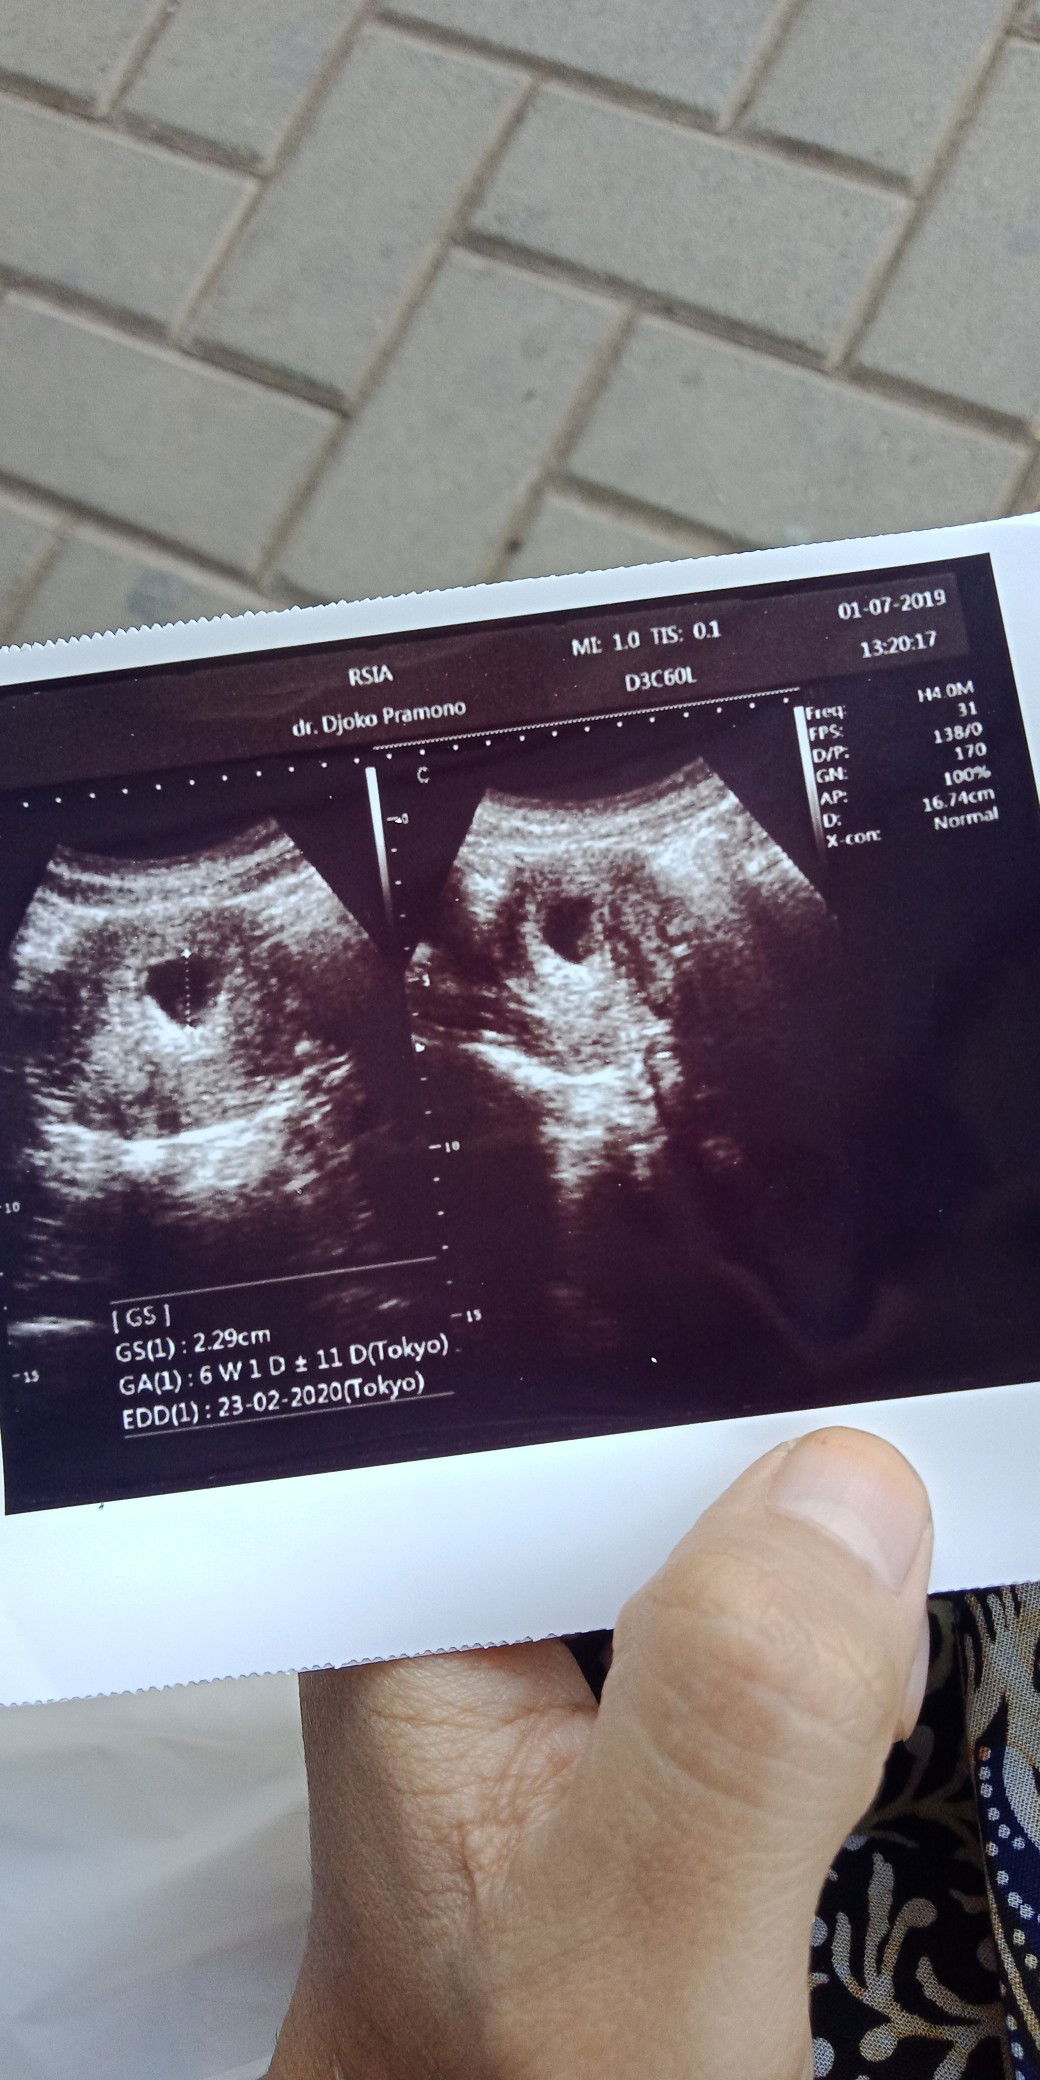

sedang mengandung

usg

Siang bunda, Maav mau tanya lg nie Pas malam sabtu akubdi usg, vonis dokter katanya janin nya udah meninggal, Tpi tadi di usg lg dengam dokter yg beda, tapi si janin masih ada, Mnrut bunda gmna ya?

Kalo tesepek masih garis 2. Tapi sudah di vonis meninggal dan suruh kuret, Apa masih ada kemungkinan?? Masih nunggu jadwal dokter usg bunda, Makasih

Semalem dokter memvonis janin sudah meninggal, dan ga ada detak jantung nya, Terus di urut, kata ma paraji janin nya baik2 aja, dan belum saat nya ada detak nya, karna usia nya masih kecil,, Ada lega sedikit, tapu ada parno nya juga, Menurut bunda gmna

Pagii, Bun usia kandungan aku 9 week, semalem di usg, tp dokter memvonis bayi ku sudah mati di dalem, Ibu mana yg ga hancur hatti nya di bilang gitu, Terus di saranin buat kuret,, Apa mungkin klo di coba minggu atw bulan depan s janin bkalan ada detak nya??